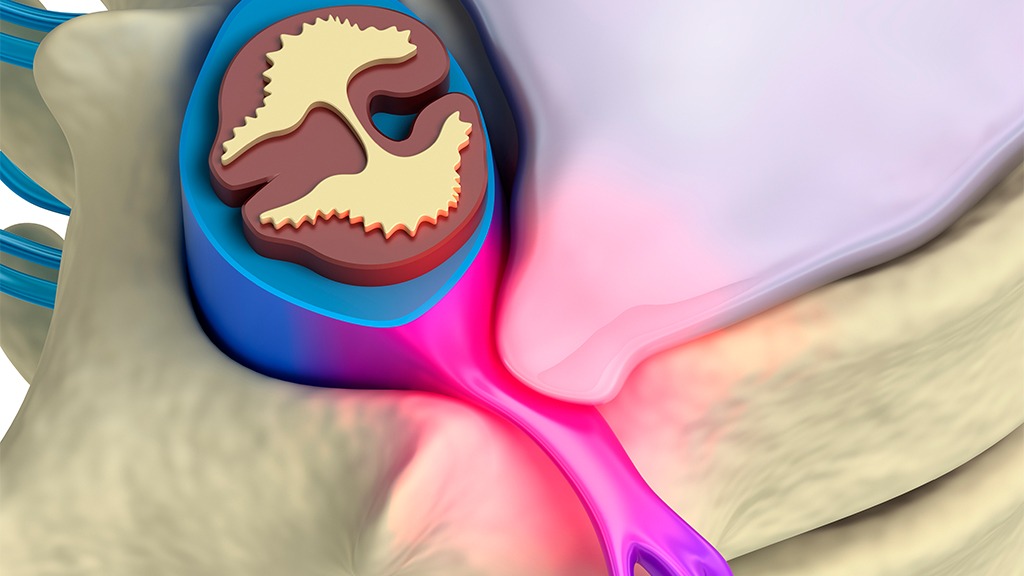

A slipped disc is not much different from a herniated or bulging disc. In fact, these terms are often used interchangeably. The difference between them is the area that is affected—the position of the disk, the condition of the cartilage, and the failure of the surrounding tissues that allow the inner fluid of the disc to penetrate the tissue and leak into the surrounding area, which may cause an enormous amount of pain and discomfort. However, some people do not experience much pain from a slipped disc, and the majority of people do not need surgery, despite recommendations for such a procedure. The most common signs that a person might be suffering from a disc problem are numbness and tingling in the arms and legs, which are often accompanied by sharp, shooting pains.

At Neck Pain, Back Pain, & Headache Relief Center in Fort Myers, our Spinal Decompression Therapy is specifically designed to help conditions such as slipped or herniated disc. Spinal Decompression is a nonsurgical procedure that involves slowly stretching the spine with the intention of relieving back and leg pain. By stretching the spine, spinal decompression aims to allow the flow of fluids and nutrients to recirculate in the affected area through negative intradiscal pressure, which promotes natural healing from the release of pressure to the spine.